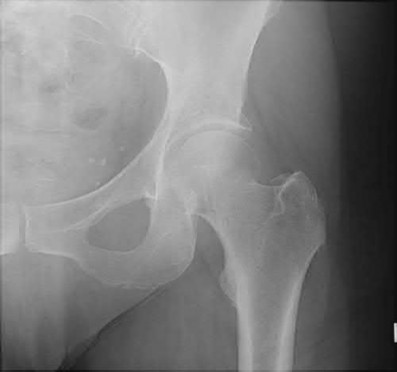

ORTHOPEDIC MCQS ONLINE 20 OB TRAUMA 1C Figure A Buttress plating is most appropriate in which of the followin…